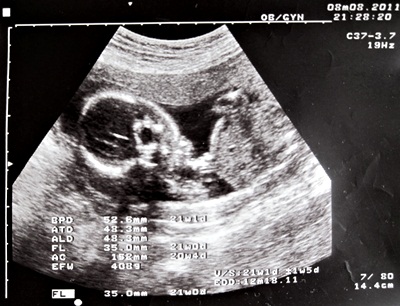

21w1d.JPG

(21w1d)

上天還是有聽到我的心聲,21W的那天產檢陳醫師宣布是個女孩兒,

說到健康,上一次的唐氏症母血篩檢的結果讓我們緊張了許久,

終於到了22周預約的詳細超音波時間,

醫師仔細地檢查了小兔仔的腦與脊椎,結果都在標準值,並沒有小腦也沒有脊椎缺損情形,

這下子與老公兩個人終於可以稍微放鬆了,不過還是每天心裡與小兔子喊話要健康長大,